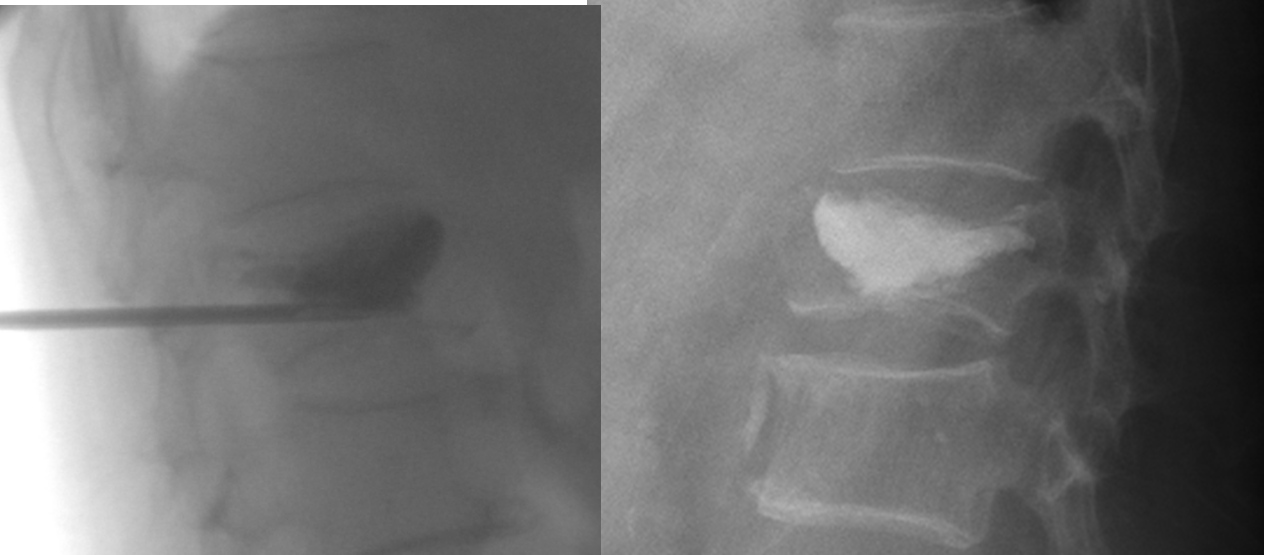

척추성형술: 이러한 최소 침습적 시술은 통증을 완화하고 뼈를 안정시키며 이동성을 향상시킵니다. 척추성형술 동안 담당 의사는 척추뼈에 바늘을 삽입하고 골시멘트를 주입합니다. 척추풍선성형술 중에는 시멘트로 채울 수 있는 팽창 장치를 삽입합니다. 척추 성형술이나 척추 풍선 성형술은 외래 시술이므로 당일 퇴원하게 됩니다.